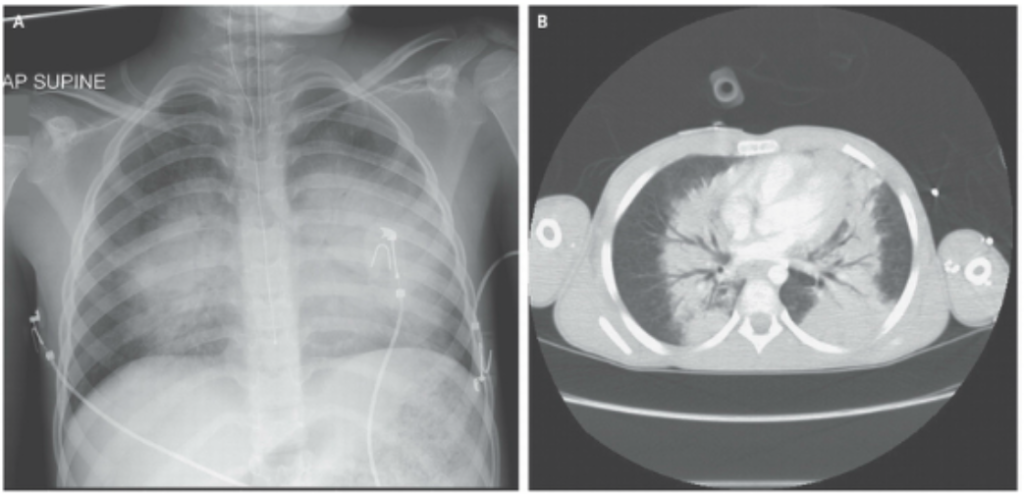

The images below show a diagrammatic representation of a blast wave passing through a cross-sectional CT scan of a chest, as well as an actual (paediatric) blast lung casualty on X-ray and CT scan (Barnard & Johnson 2013). The fluffy-looking opacities radiating out from the centre of the X-ray and CT scan are caused by the blast-damaged lung leaking fluid into the air spaces.

Of the surviving three, one, the child’s mother, had severe spinal injuries and was rendered densely paraplegic from the mid-chest down. The other survivor, the little girl’s toddler brother had open injuries to his abdomen, had lost toes and fingers and had an open skull fracture with his brain on show (pictured below in Tertiary Blast Injury). Despite the devastation of the blast, the little girl had seemingly no more injuries than a superficial graze to her forehead. It was suspected that the mother had been cradling her at the time of the event and had shielded her from the blast. Whilst it initially appeared as a miracle, the little girl began to develop significant breathing difficulties within 24 hours of injury and despite intubation and ventilation to try and manage her lung injury; she deteriorated and died by the 48-hour mark.

Barnard, E, Johnston, A 2013, ‘Images in clinical medicine. Blast lung’, New England Journal of Medicine, vol. 14, no. 383(11), p. 1045.